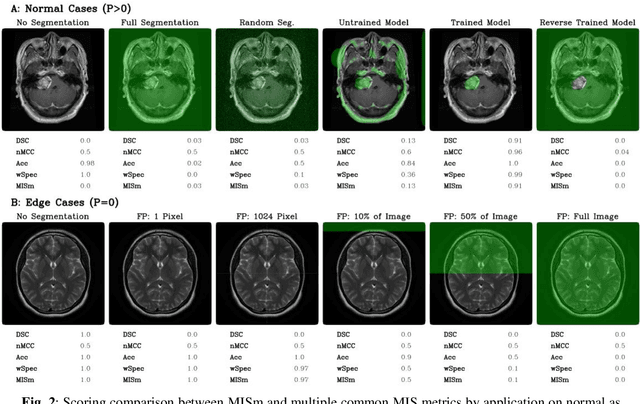

Performance measures are an important tool for assessing and comparing different medical image segmentation algorithms. Unfortunately, the current measures have their weaknesses when it comes to assessing certain edge cases. These limitations arouse when images with a very small region of interest or without a region of interest at all are assessed. As a solution for these limitations, we propose a new medical image segmentation metric: MISm. To evaluate MISm, the popular metrics in the medical image segmentation and MISm were compared using images of magnet resonance tomography from several scenarios. In order to allow application in the community and reproducibility of experimental results, we included MISm in the publicly available evaluation framework MISeval: https://github.com/frankkramer-lab/miseval/tree/master/miseval